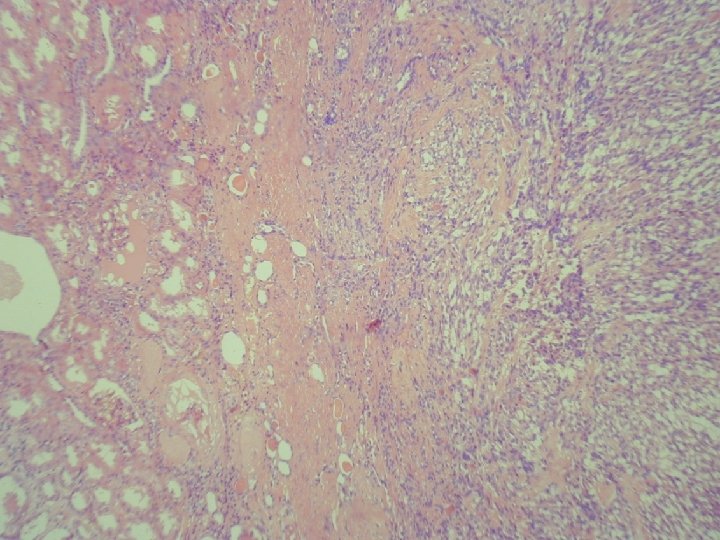

Klinické údaje: • 76 -ročný muž sledovaný pre tumor močového mechúra, na CT zachytený tumor pravej obličky priemeru 4 cm • makro: sivočervený, dobre ohraničený, s drobnými dutinkami, subkapsulárny

Mucinous tubular and spindle cell carcinoma.

• LG polymorfný renálny tumor: mucinózny, tubulárny, spindle cell • 17 – 82 rokov • M/Ž– 1/4 • v minulosti: neklasifikovaný alebo sarkomatoidný